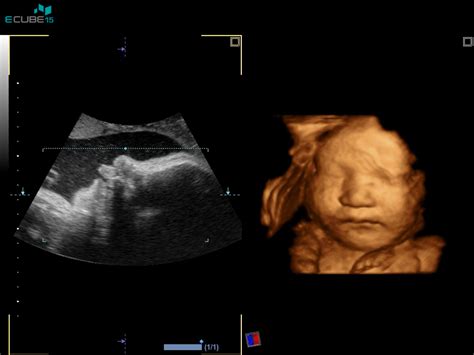

Natančna UZ ocena morfologije ploda je ena od najpomembnejših preiskav v nosečnosti, običajno opravljena med 20. in 22. tednom nosečnosti (nekatere smernice navajajo tudi med 19. in 23. tednom). Namenjena je predvsem potrditvi normalnega razvoja ploda oziroma odkrivanju večjih razvojnih nepravilnosti ter t.i. "mehkih" označevalcev, ki povečajo tveganje za prisotnost kromosomske napake pri plodu. V tem času je razvoj plodovih organov večinoma že zaključen, kar z veliko verjetnostjo omogoča napoved rojstva zdravega otroka.

Med morfologijo se natančno pregledajo vsi organski sistemi ploda: glava, možgani, obraz (vključno z izključitvijo zajčje ustnice), hrbtenica, srce, pljuča, prepona, želodec, ledvički, sečni mehur, sprednja trebušna stena, okončine (preštejejo se prstki na rokah in nogah). Pregleda se tudi lega posteljice, število žil v popkovnici in oceni količina plodovnice. V primeru normalnega izvida se lahko z veliko verjetnostjo napove rojstvo zdravega otroka. Izjema so pljuča in možgani, katerih razvoj se nadaljuje tudi po rojstvu, zato je nevrološka ocena ploda nekoliko manj zanesljiva. V tem času se lahko spremeni predviden datum poroda (PDP), če se rast ploda ne ujema s pričakovanji. Na željo se lahko določi tudi spol otroka.